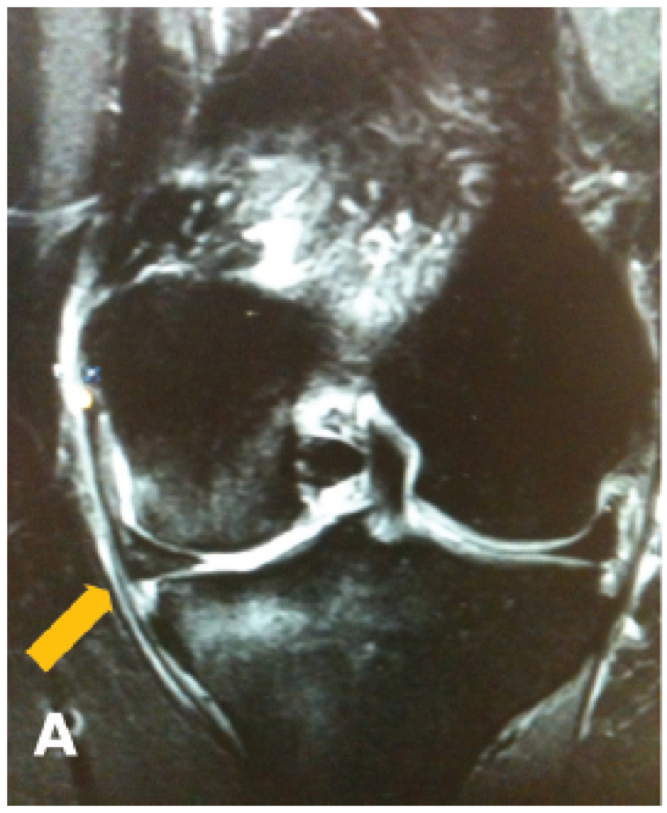

MRI

Findings

- meniscal extrusion

- meniscal ghost sign on sagittal (missing meniscus)